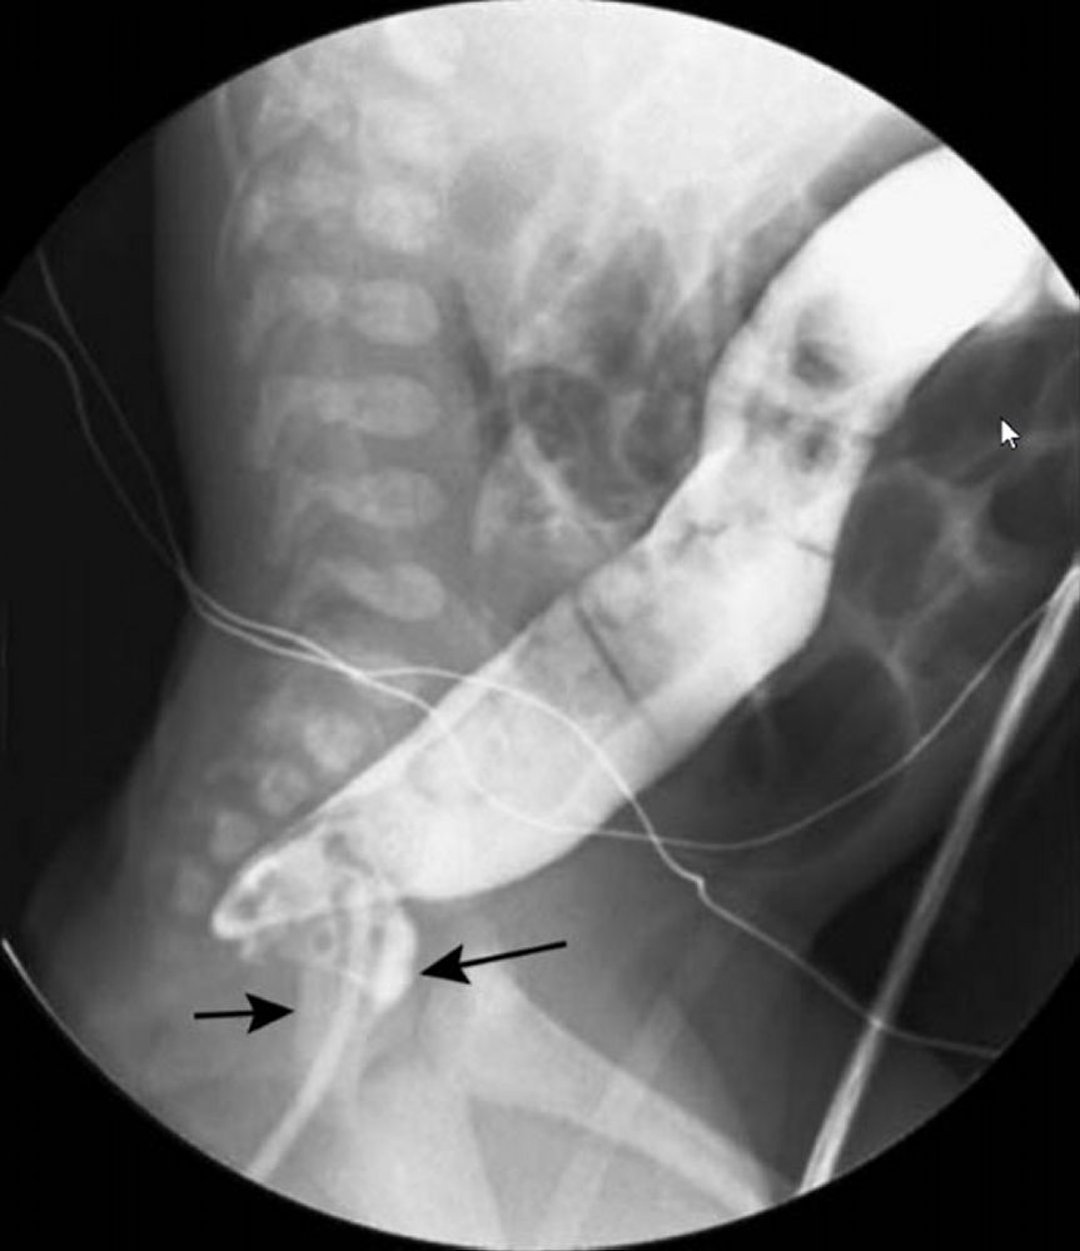

Hirschsprung disease (short segment type) Image Radiology Barium Enema Radiology Hirschsprung Disease to determine the relative accuracy of the various radiologic signs of hirschsprung disease (hd), we retrospectively reviewed. barium contrast enema (be) is the primary imaging modality for the evaluation of clinically suspected cases. To evaluate sensitivity, specificity, positive predictive value, and negative predictive value of radiologic findings for. barium contrast enema (be) is the primary imaging modality. Radiology Barium Enema Radiology Hirschsprung Disease.